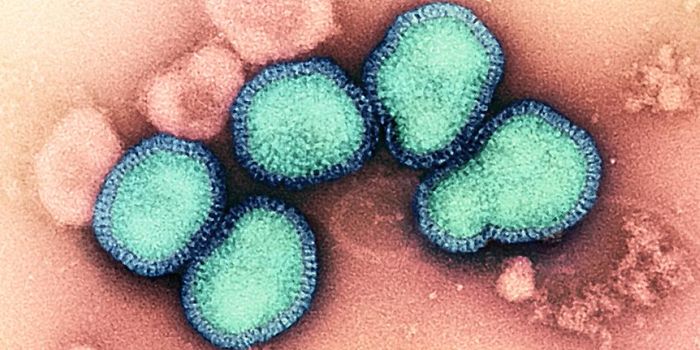

NOV 17, 2021MicrobiologyEvery year, there is a flu outbreak, and the severity can depend on many factors, like what strain is circulating. Last ...